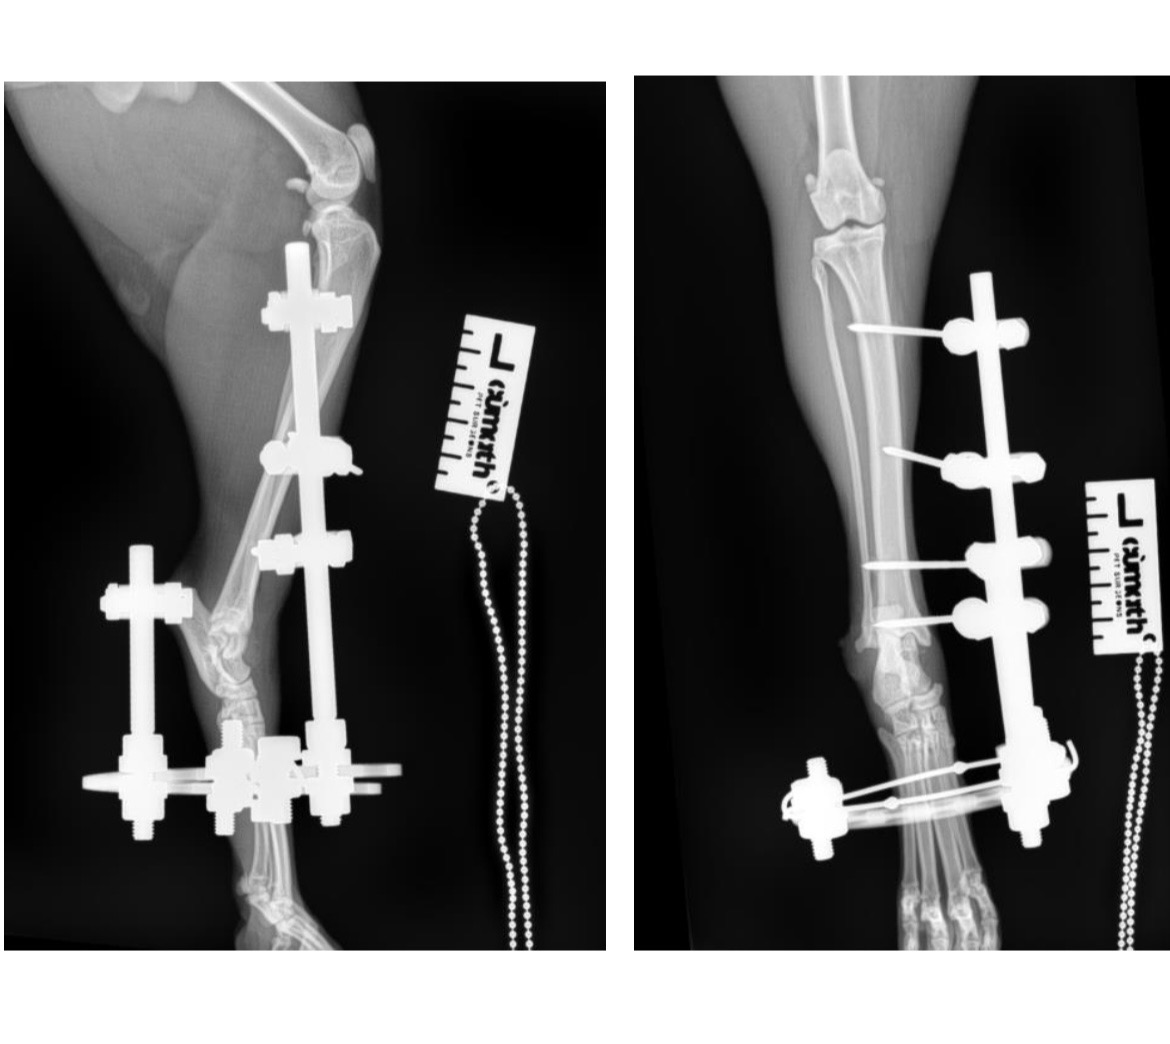

He crawled home with a severely broken leg, the vet thinks he was hit by a car when he first went missing.

He has been referred to a different vet for surgery to try and save his leg with a rough estimate of £3000.